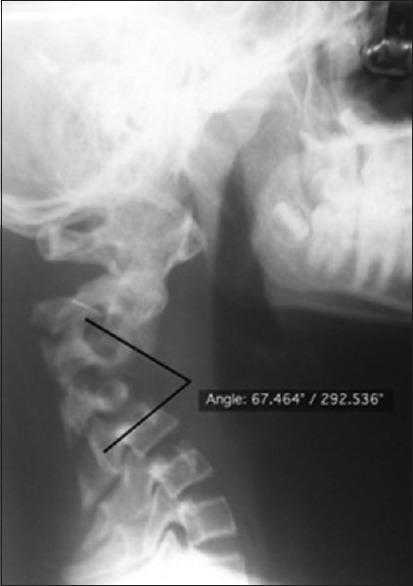

A 14-year-old boy presented with gradually worsening spastic quadriparesis and cervical kyphotic deformity as a consequence of laminectomy for tumor debulking and chemoradiotherapy done 2 years prior for cervical primitive neuroectodermal tumor. Problems to be addressed particularly to the case were a rigid kyphosis of 102.7°, poor soft-tissue coverage, internal gibbus compressing cord, perched facets, and superficial location of cord. The surgery was staged, in that the first anterior release was done with gradually increasing traction to correct the kyphosis progressively. Posterior instrumentation was done in the second stage. Finally, anterior reconstruction with tricortical iliac bone grafting was done. The patient regained full power with complete union at the end of 18 months. Irradiation of tumor along with laminectomy results in loss of posterior tension band which results in progressive kyphotic deformity in children. A staged plan of surgical interventions can help in postoperative correction of deformity with circumferential union and prevention of recurrence. This article describes successful treatment of a patient with postlaminectomy cervical kyphosis with 77° of correction achieved postoperatively and also highlights the importance of anterior and posterior reconstructions to achieve a stable vertebral column.

一名14岁男孩因两年前为治疗颈椎原始神经外胚层肿瘤而进行的肿瘤减瘤椎板切除术和放化疗,出现逐渐加重的痉挛性四肢瘫和颈椎后凸畸形。该病例需要特别解决的问题包括102.7°的僵硬后凸、软组织覆盖差、内部驼背压迫脊髓、关节突高位以及脊髓位置表浅。手术分阶段进行,首先进行前路松解,逐渐增加牵引以逐步矫正后凸。第二阶段进行后路内固定。最后,进行三皮质髂骨移植的前路重建。患者在18个月结束时恢复了全部肌力,实现了完全愈合。肿瘤放疗联合椎板切除术会导致后张力带丧失,从而导致儿童出现进行性后凸畸形。分阶段的手术干预计划有助于术后通过环形愈合矫正畸形并预防复发。本文描述了一名椎板切除术后颈椎后凸患者的成功治疗,术后实现了77°的矫正,同时强调了前后路重建对于实现稳定脊柱的重要性。